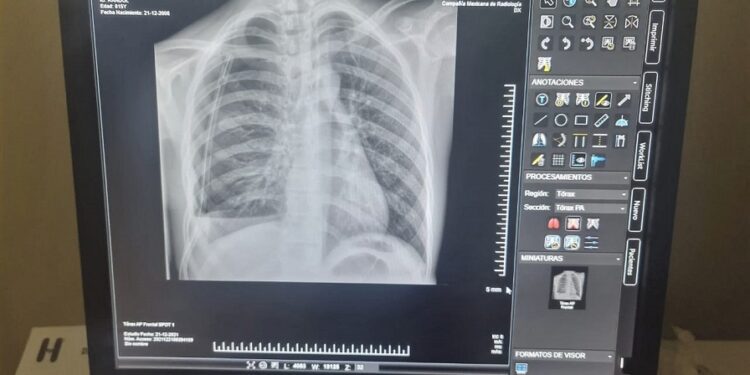

SANTO DOMINGO.- El hospital pediátrico, doctor Robert Reid Cabral, informó que instaló un moderno equipo de rayos X para brindar servicios de radiología digitalizada a sus usuarios con calidad.

El doctor Clemente Terrero, director del centro de salud, destacó en un comunicado de prensa que con la instalación del dispositivo de rayos X, en la que se gastaron más de dos millones de pesos, se deja atrás el obsoleto equipo análogo que operó en el hospital durante más de 65 años.

Dijo que el equipo de rayos X cuenta con una estación de trabajo y una impresora digital para el técnico, “y además se instalará una computadora con su monitor en la estación del médico radiólogo para que este realice las lecturas de los estudios”.

“Aseguramos con orgullo que, de los hospitales públicos tradicionales, el hospital Robert Reid Cabral es de los pioneros en digitalizar el servicio de radiología”, subrayó Terrero.

Dijo que era necesario instalar nuevo equipo de rayos X, “y al evaluar las condiciones de los equipos que contábamos, que ya agotaron su vida útil, y los técnicos nos recomendaron adquirir un dispositivo de punta digital, que nos va ahorrar costo ya que no se comprarán placas ni químicos para revelar las imágenes”.